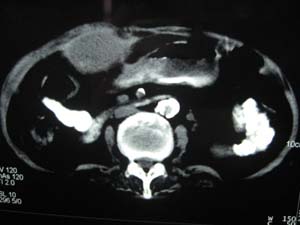

标题: CT15625:女性78Y,十天前胃镜示胃穿孔,现低热 [打印本页]

标题: CT15625:女性78Y,十天前胃镜示胃穿孔,现低热

膈下脓肿

支持--膈下脓肿

膈下及肝脓肿。

考虑多发性肝脓肿。